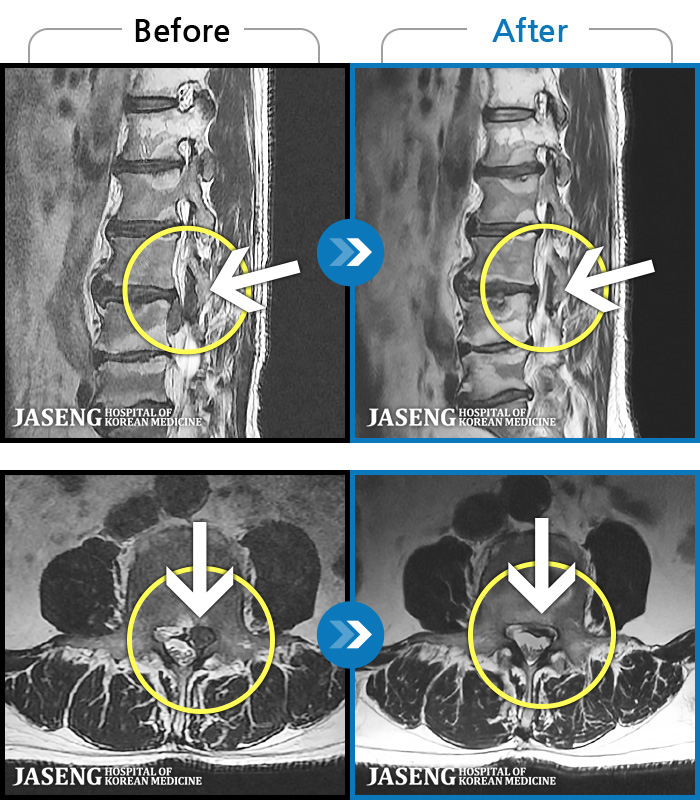

- MRI ġ

MRI ġ

MRI ũ ʸ Ȯϼ.